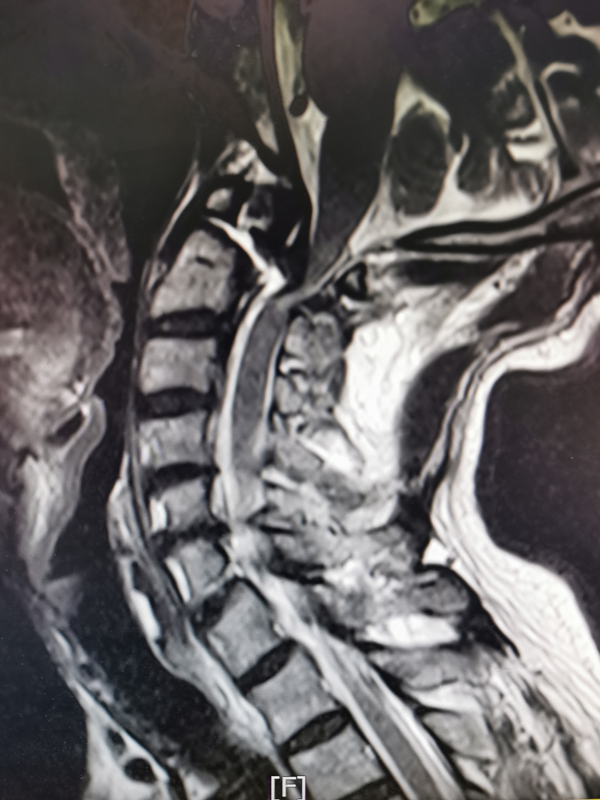

该患者今年82岁,受伤原因为不慎从 2 米多梯子上摔落,导致浑身多处疼痛,颈项部疼痛难忍,遂前来我院门诊就诊。后逐步出现双手臂麻木、无力,双手握东西都觉得没力、持物不稳。骨三科张纯主任医师、王伟卓副主任医师诊断他的伤病为枢椎齿状突Ⅱ型骨折。接诊后立即给予激素稳定神经细胞膜及脱水治疗,并同时予以头颈部制动牵引。

在完善相关检查后,张纯主任医师组织骨三科科医生团队讨论患者病情。枢椎齿状突骨折是颈椎外伤中的一种严重损伤,如果处理不当会导致寰枢椎不稳定、半脱位甚至脱位,压迫延髓,造成高位脊髓损伤,甚至危及生命。对枢椎齿状突骨折患者治疗有保守疗法和手术治疗。高龄患者若采取保守治疗,一是需要患者长期卧床、持续颅骨牵引,并发症多,很快会危及患者生命;而且Ⅱ型齿状突骨折保守治疗存在较高的不愈合风险。若采用手术方式则风险较大,上颈椎(即寰枢椎)手术为脊柱骨科最高风险手术之一,被称为脊柱外科手术上的明珠,因颈部后方显露位置深在,椎管内为延髓,椎弓旁边有椎动脉,任何操作失误都将造成严重后果甚至危及生命,同时该类手术对麻醉、体位及手术操作都有很高的要求。况且该患者高龄,存在心脑血管风险不言而喻,对麻醉手术都是很大挑战,要求手术快速、精细、微创,尽量维持患者血流动力学稳定。